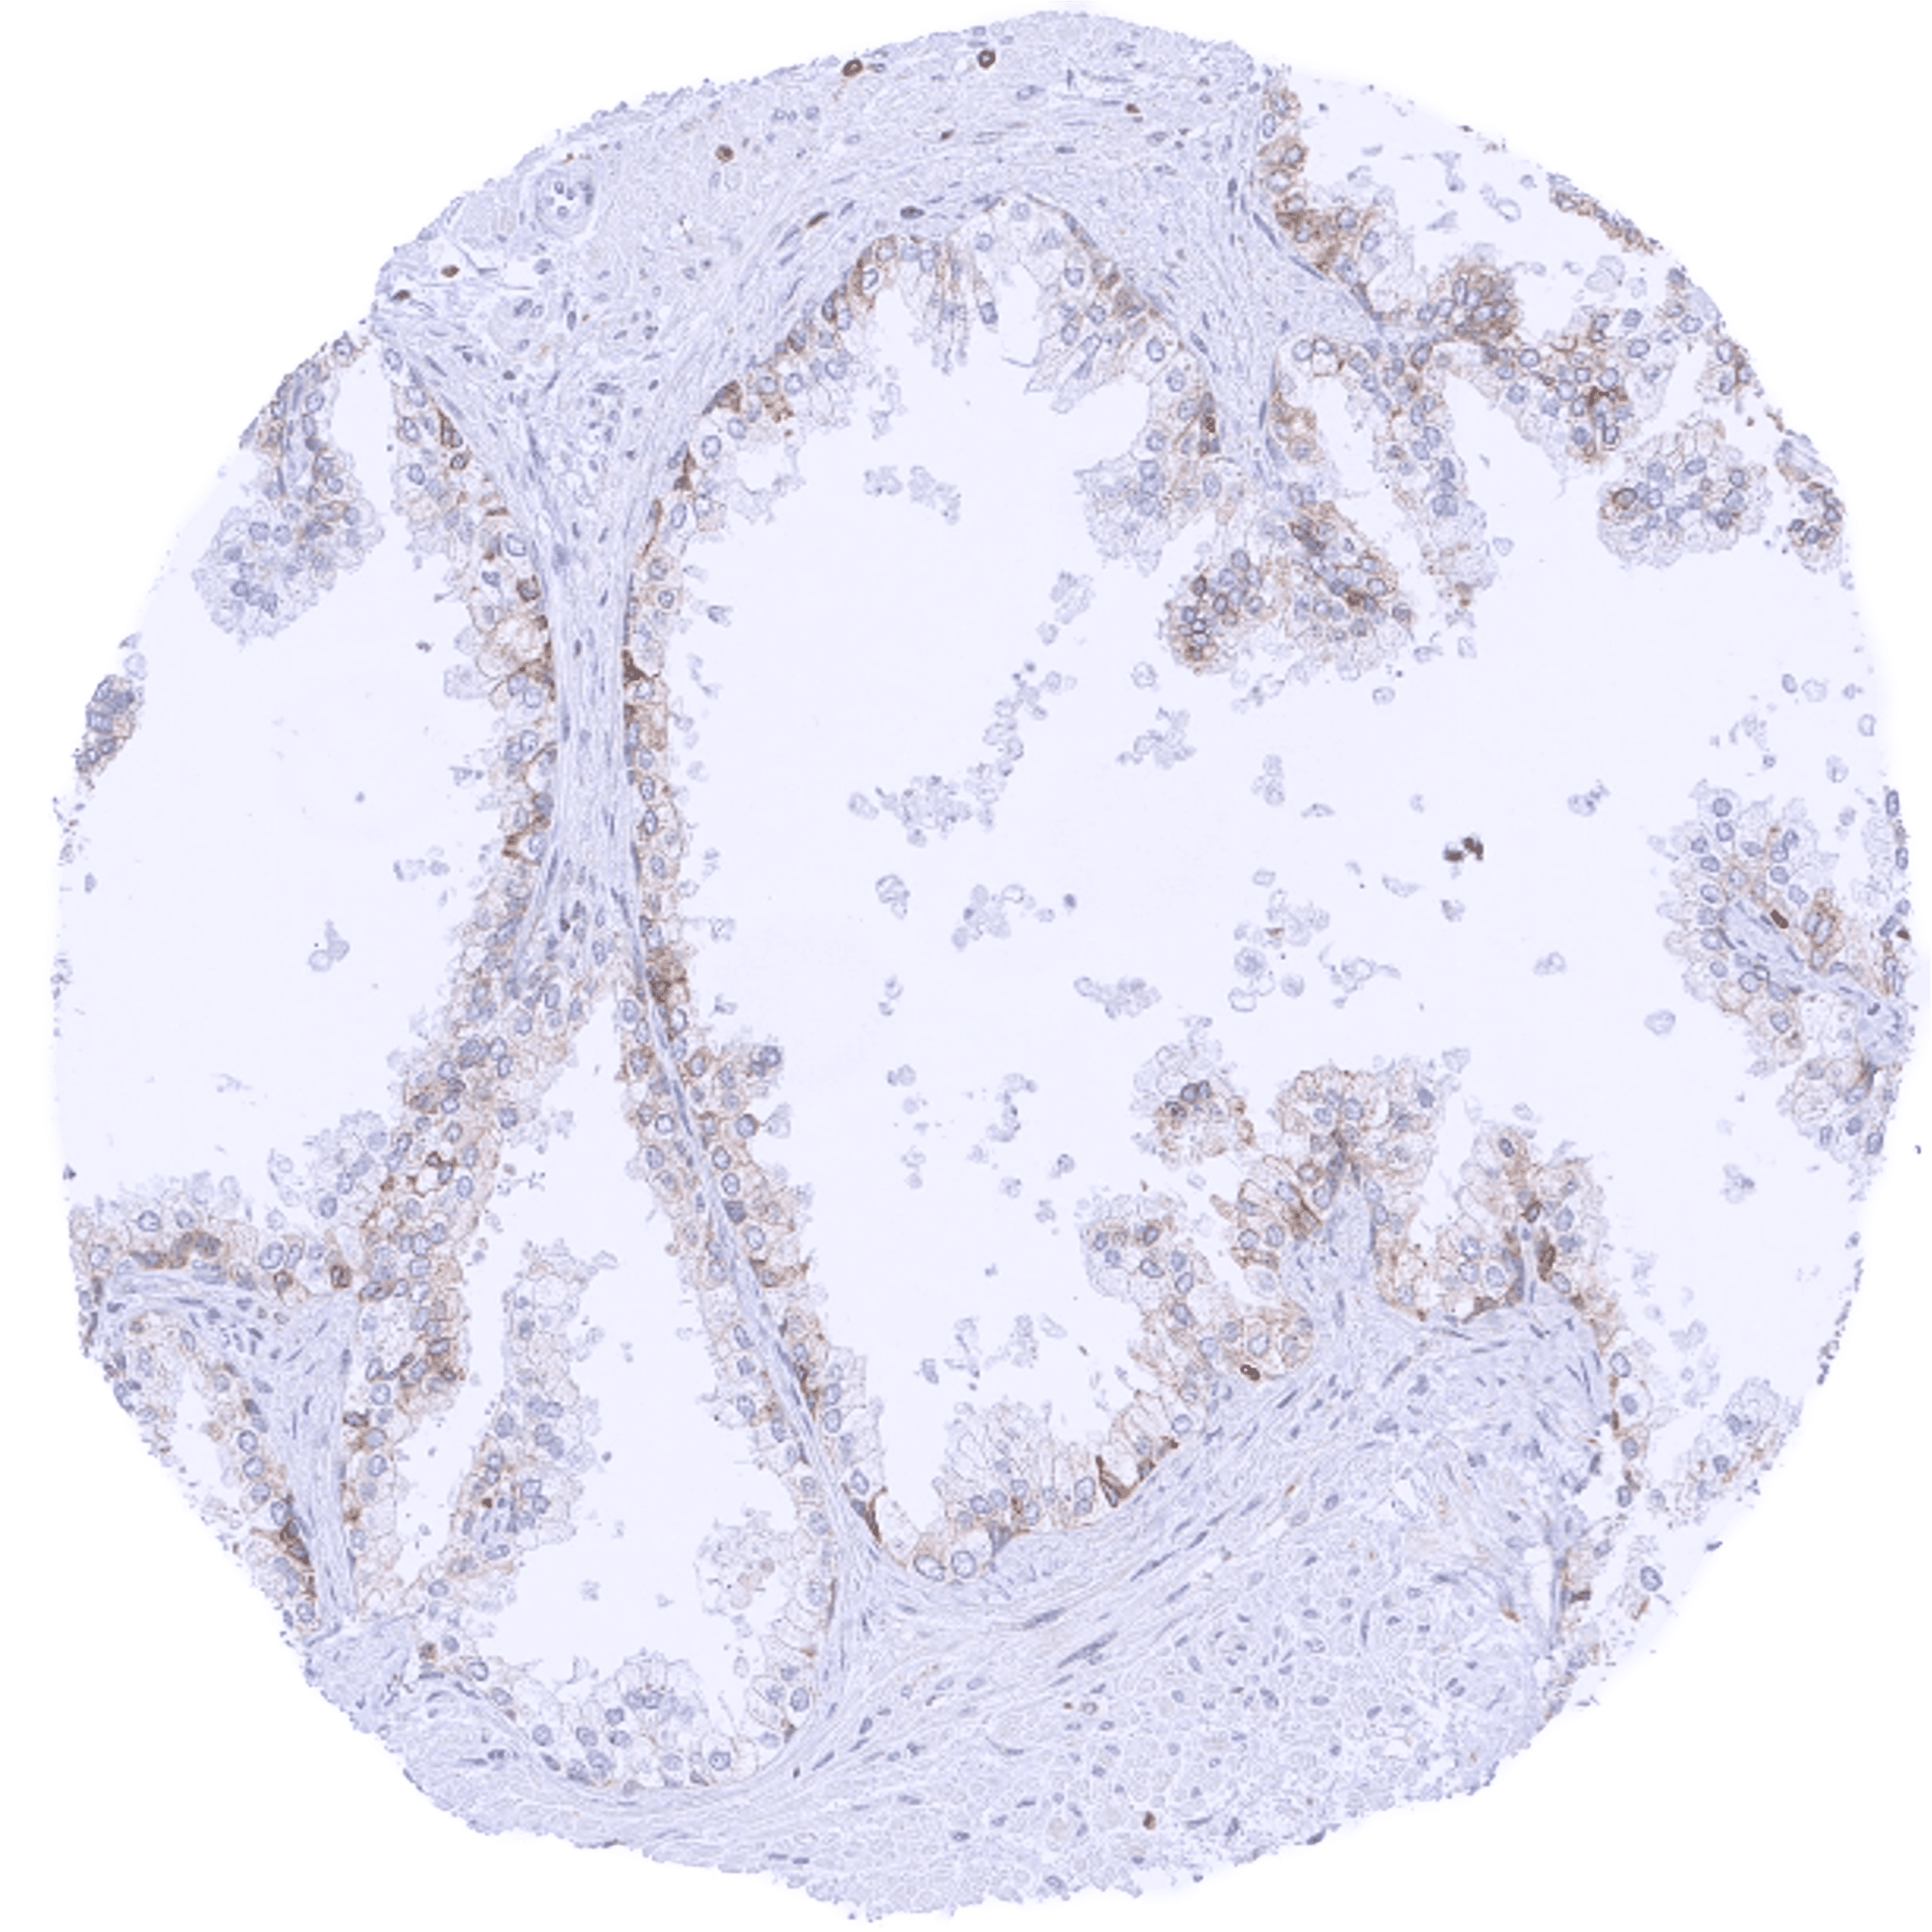

Bcl-2 expression of variable intensity can occur in all types of cancer. It is particularly common in follicular lymphoma.

Comparison of antibodies: True expression of bcl-2 in all cell types with documented bcl-2 immunostaining by MSVA-402M is validated by identical staining patterns obtained by a second, independent commercially available bcl-2 antibody, termed “validation antibody” for all analyzed tissues.